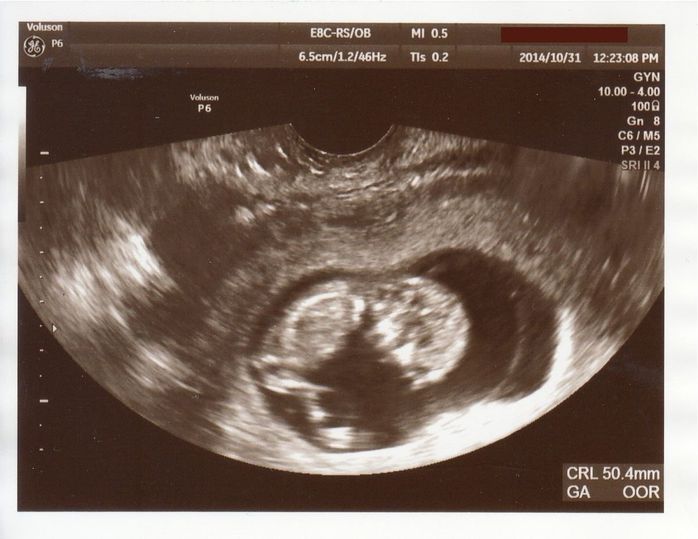

<妊娠初期> 妊娠7週目~12週。待ち望んだ、3人目の赤ちゃん。

無事に胎嚢と心拍を確認 - 妊娠7週目のエコー写真

しばらく生理が来ないなと思って、妊娠検査をしたら陽性。1週間ほど経って都合のよい日に、上の子を出産した産院に行きました。左下の黒い丸が胎嚢、その中の小さな白いものが赤ちゃん。まだ胎芽と呼ばれる状態です。妊娠確定! エコーで胎嚢と心拍を無事に確認できたので安心しました。私も夫も3人兄弟。できれば子どもは3人欲しかったので、とても喜ばしい出来事でした。